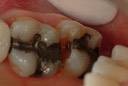

Wayne Chin #31 pre-op